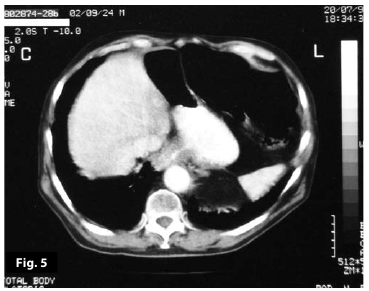

Figure5